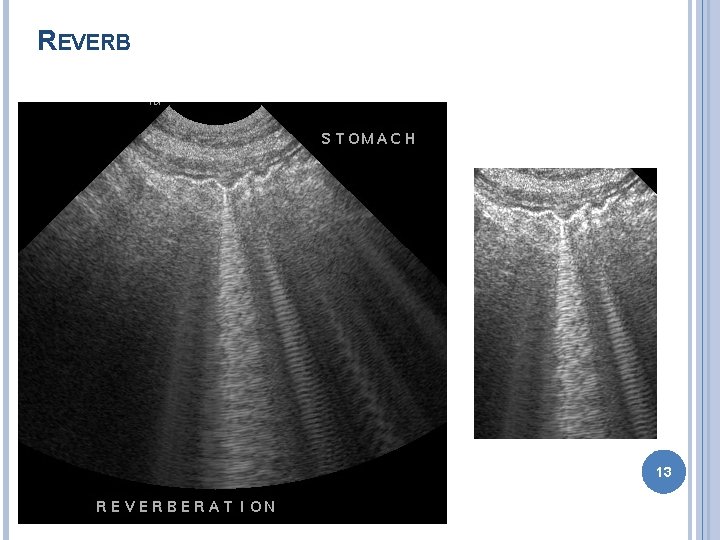

ARTIFACTS Improper machine settings – gain Reverberation � Mirror image – liver GB � Comet tail – gas bubble � Ring down – skin transducer surface Acoustic shadowing Acoustic enhancement Edge enhancement � Border of kidney 11

REVERB 13